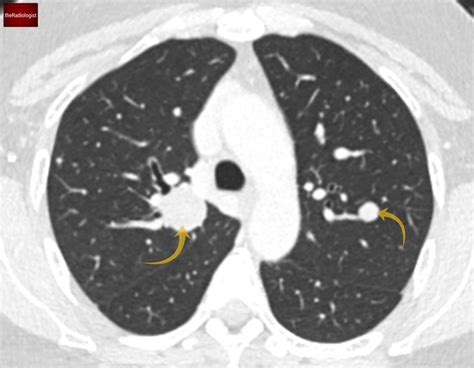

Lung nodules are typically discovered incidentally during imaging tests performed for other reasons. They can be classified based on their size, shape, and composition. The most common types include:

• Solid Nodules: These are dense and appear white on imaging scans.

• Ground-Glass Nodules: These have a hazy appearance and are less dense than solid nodules.

• Part-Solid Nodules: These contain both solid and ground-glass components.

• Cavitary Nodules: These have a central area of low density, resembling a cavity.

• CT Scan: Computed tomography (CT) scans provide more detailed images and are crucial for evaluating the size, shape, and density of lung nodules.

When evaluating pictures of lung nodules, radiologists look for specific characteristics that can indicate the nature of the nodule. These characteristics include:

• Size: Larger nodules are more likely to be malignant.

• Shape: Irregular or spiculated edges are often associated with cancer.

• Density: Solid nodules are more concerning than ground-glass nodules.

• Growth Rate: Rapidly growing nodules are more likely to be malignant.